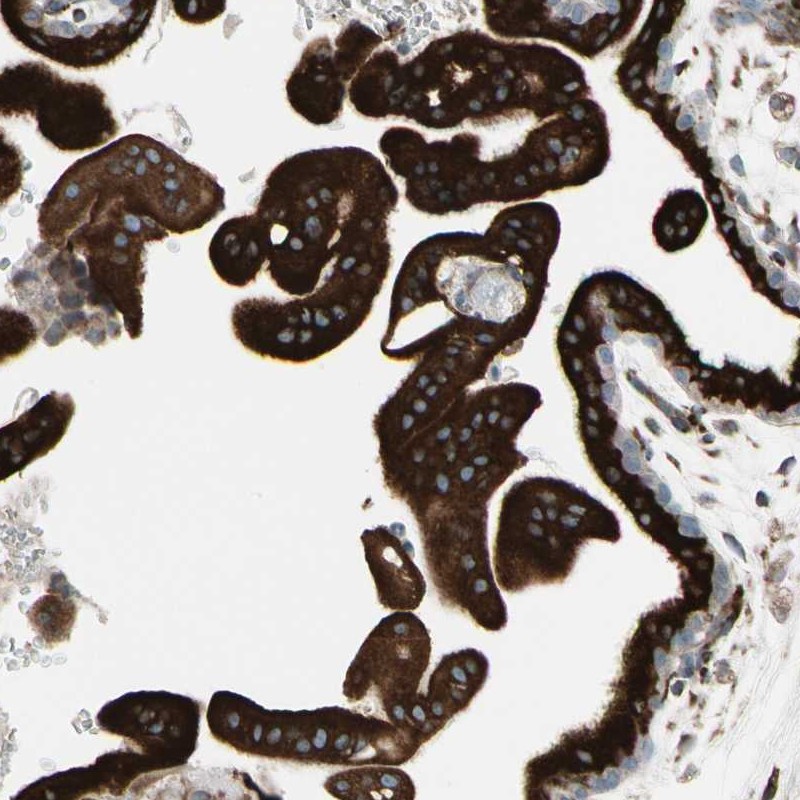

Immunohistochemical staining of human placenta shows strong cytoplasmic positivity in trophoblastic cells.